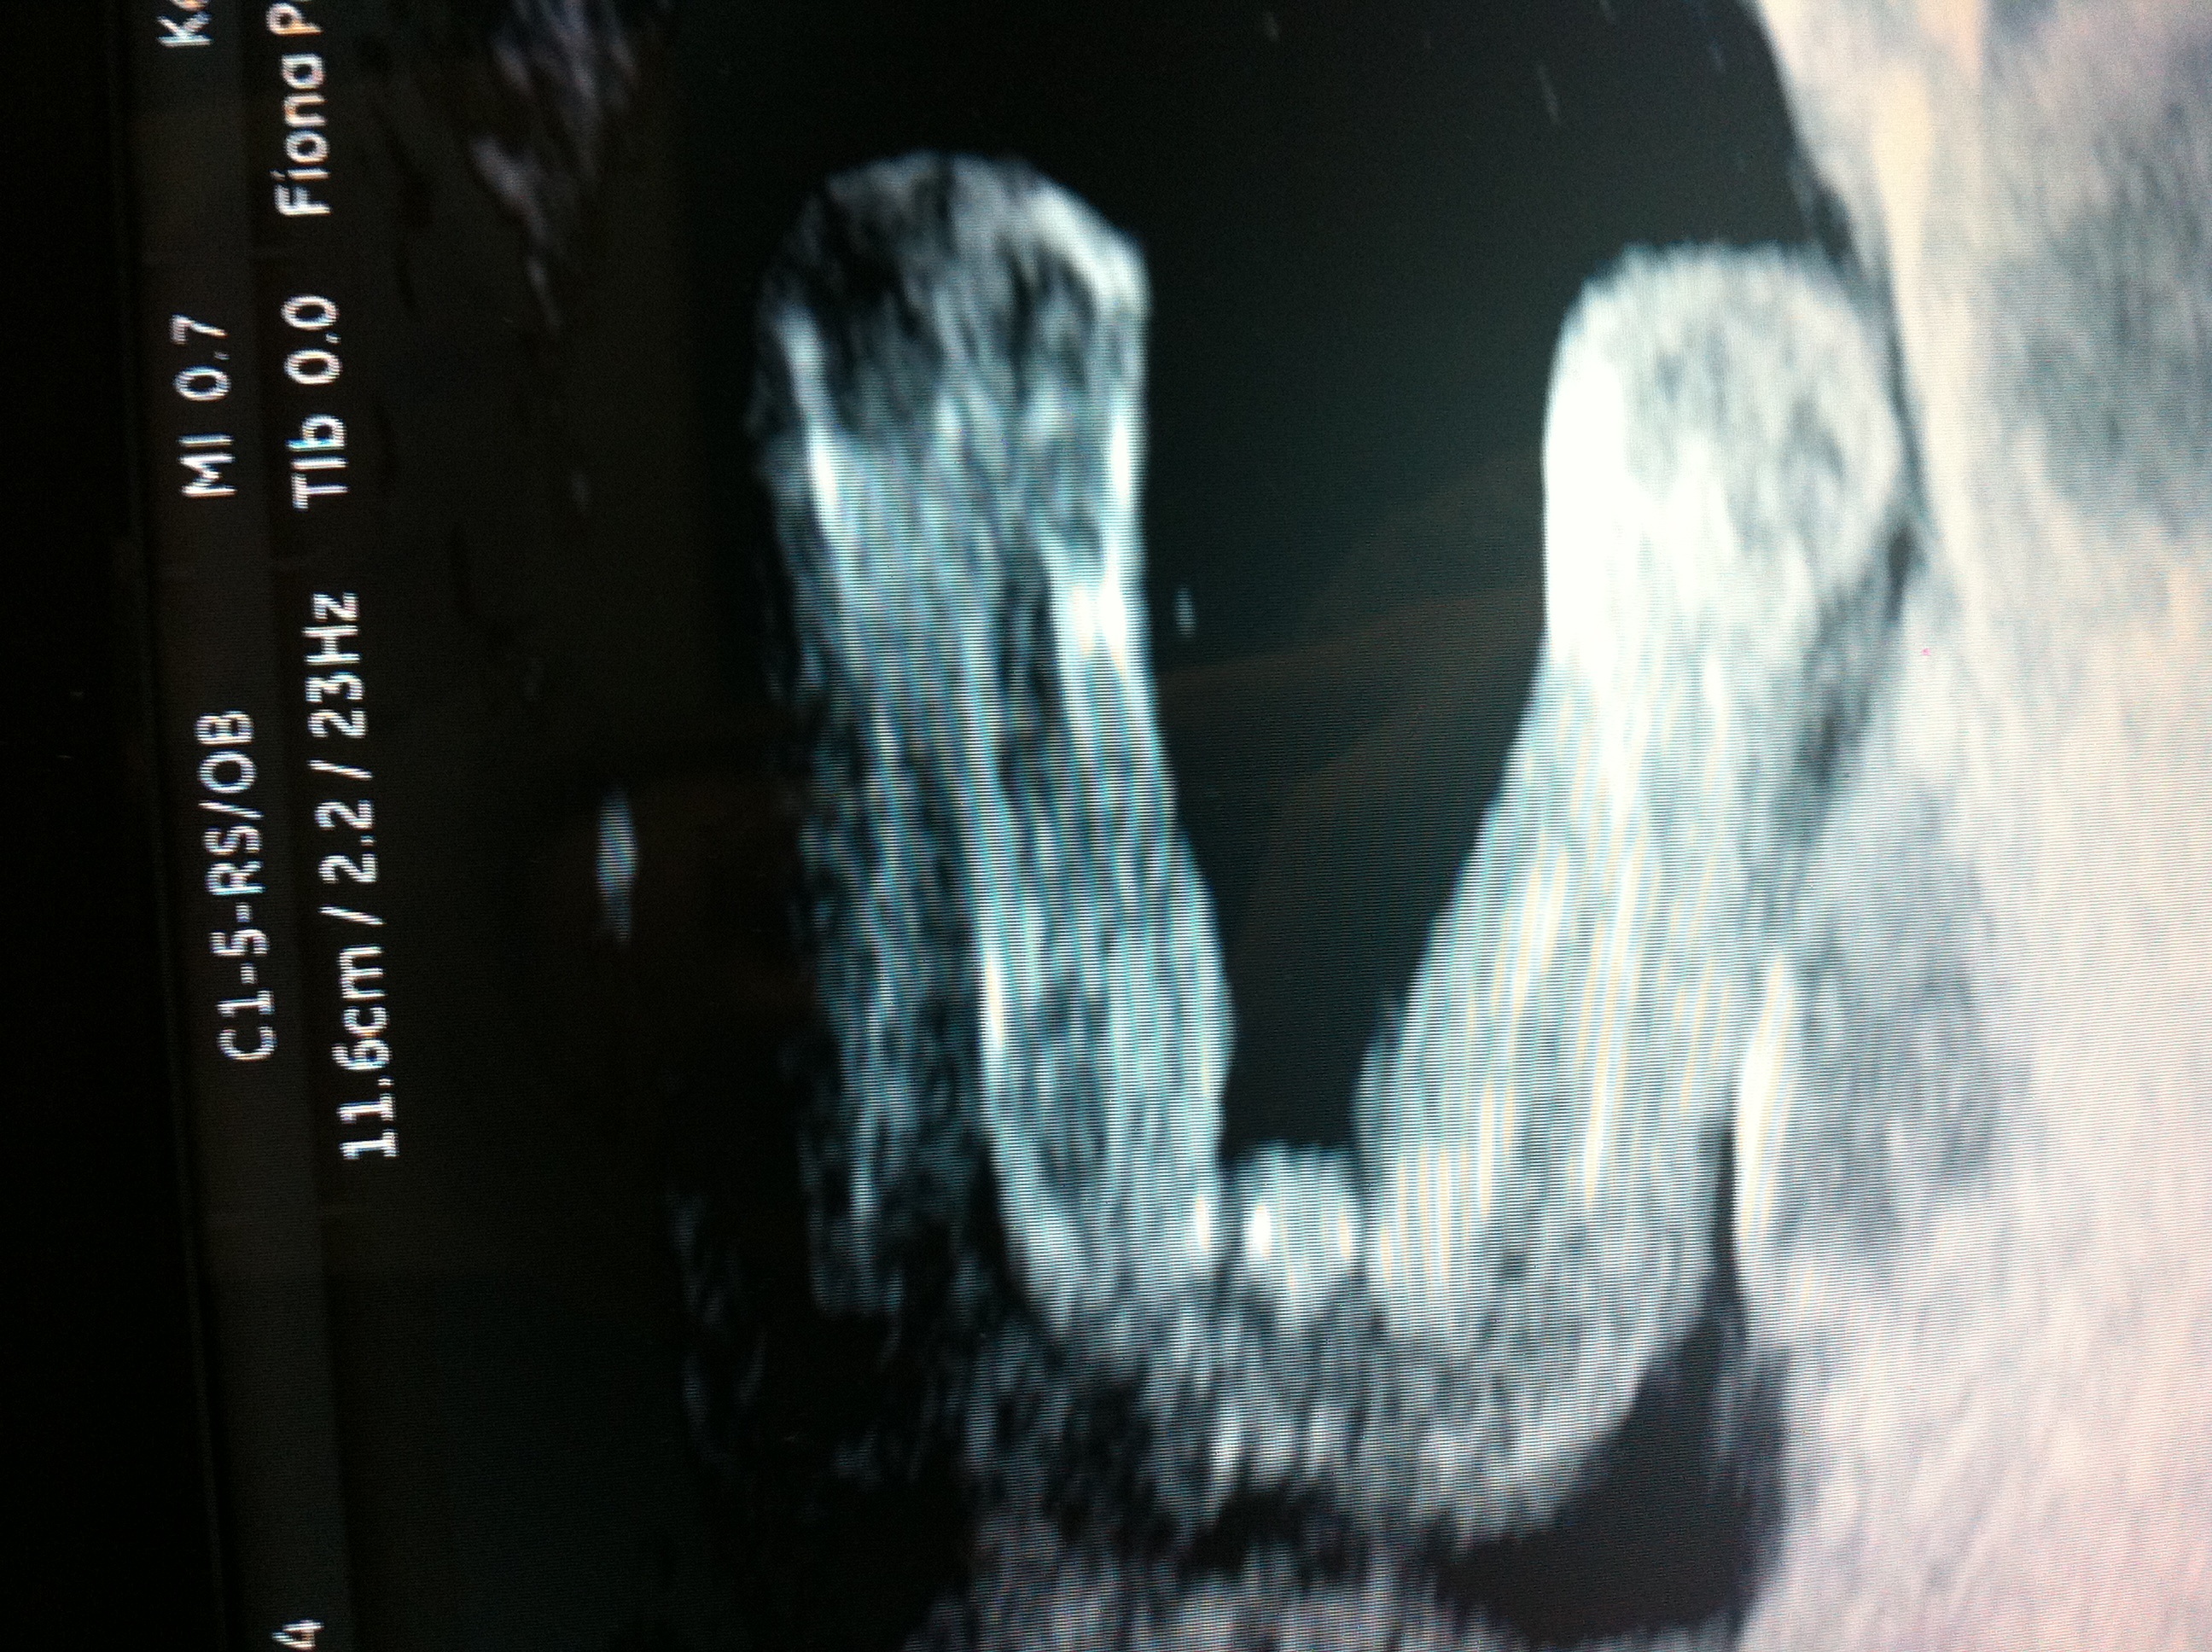

How Accurate Is A Gender Ultrasound At 17 Weeks

To evaluate the accuracy of 3D ultrasound in fetal gender assignment at first 3D ultrasound is extremely accurate in fetal gender assignment prior to 14 weeks of VSD28, AVSD 24, TGV 22, heterotaxia 17, Aorta and arch abnormalities 15, DORV 14, TOF 12 (5 with PA), hypoplastic RV 11 ... Access Content